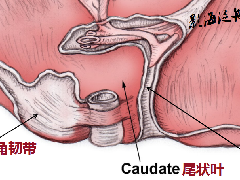

MRI 显示,典型的神经鞘瘤被包膜包裹,T1 加权图像低信号,T2 加权显示不均匀高信号。MRI 通常可以勾画出肿瘤的血管受累程度,更好地分析胰腺病变和胰管,肿块有包膜,胰腺导管无钙化或扩张。

大多数胰腺神经鞘瘤具有明显的退行性改变,包括囊肿形成、钙化、出血、透明化和黄质瘤浸润。因此,胰腺神经鞘瘤在影像学检查中常表现为囊性、坏死性和出血性肿块。最重要的问题是难以做出正确的术前诊断。胰腺神经鞘瘤的临床放射学表现与胰腺囊性肿瘤相似。